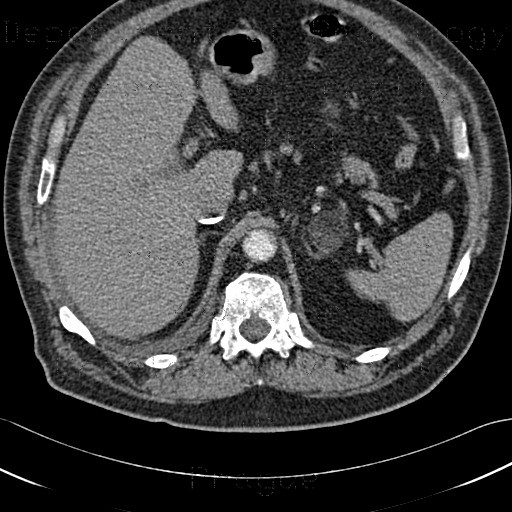

Angiomyolipoma in both kidneys (arrows) in computer tomography. The tumours are hypodense (dark) due to fat content. Myelolipoma; Myxoid liposarcoma; PEComa. Angiomyolipoma; Chondroid lipoma; Intradermal spindle cell lipoma; Pleomorphic lipoma; ... Read Article

The cut surface of an adrenal myelolipoma shows colour variegation from yellow to red to brown depending on the distribution of fat, blood and myeloid elements. In histology, variegation is the property of having discrete markings of different colors. [1] ... Read Article

Myelolipoma OftheAdrenal: TwoCaseswithUltrasound AndCTFindings

Myelolipoma oftheAdrenal: TwoCaseswithUltrasound andCTFindings adrenal calcifications andirregular calcification inthelateral margin ofthemass(fig.2A).Therightadrenal calcification was confined tothegland, andtherewerenoassociated masses to ... Retrieve Content